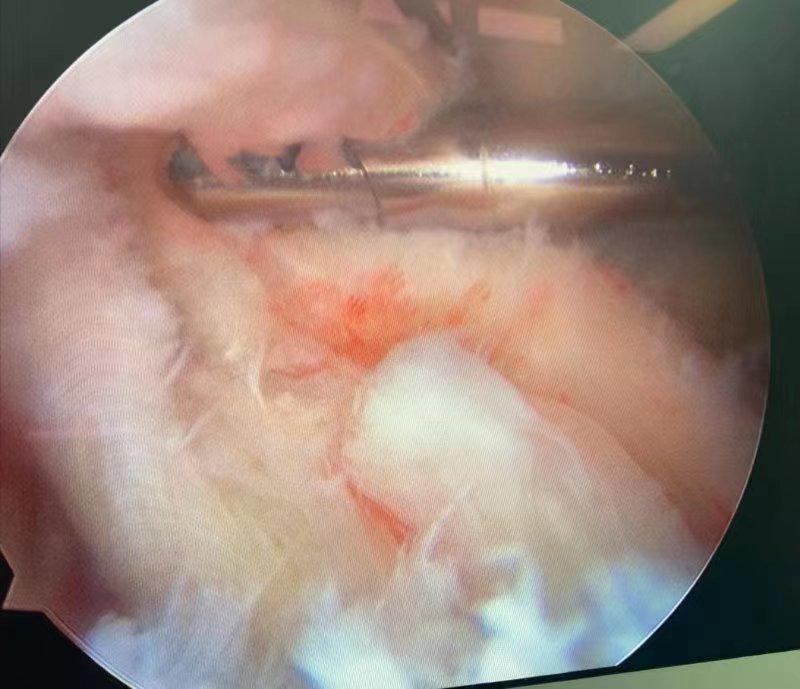

经过术前缜密计划,手术过程十分顺利, 仅用时1小时左右 ,关节镜属于微创手术,手术仅4-5个约 0.5cm小切口 ,术后恢复快。

图片二